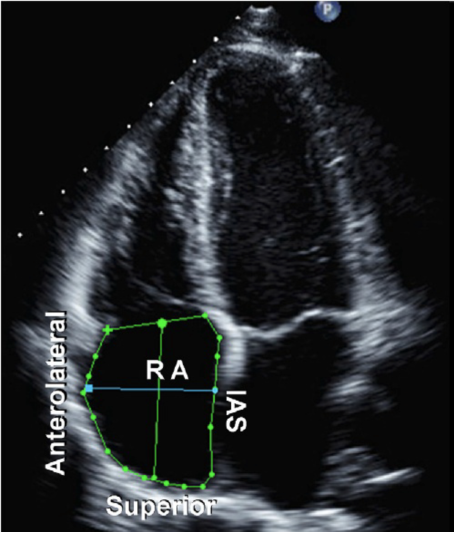

右心房一般通过心尖四腔心切面来观察形态学大小图7,其左右内径的参考值为2.5~4.5 cm,上下内径的参考值一般小于5.2 cm。

图片

图7. 右心房(RA)在A4C下(蓝色线段左右径,绿色线段上下径)内径测量示意图